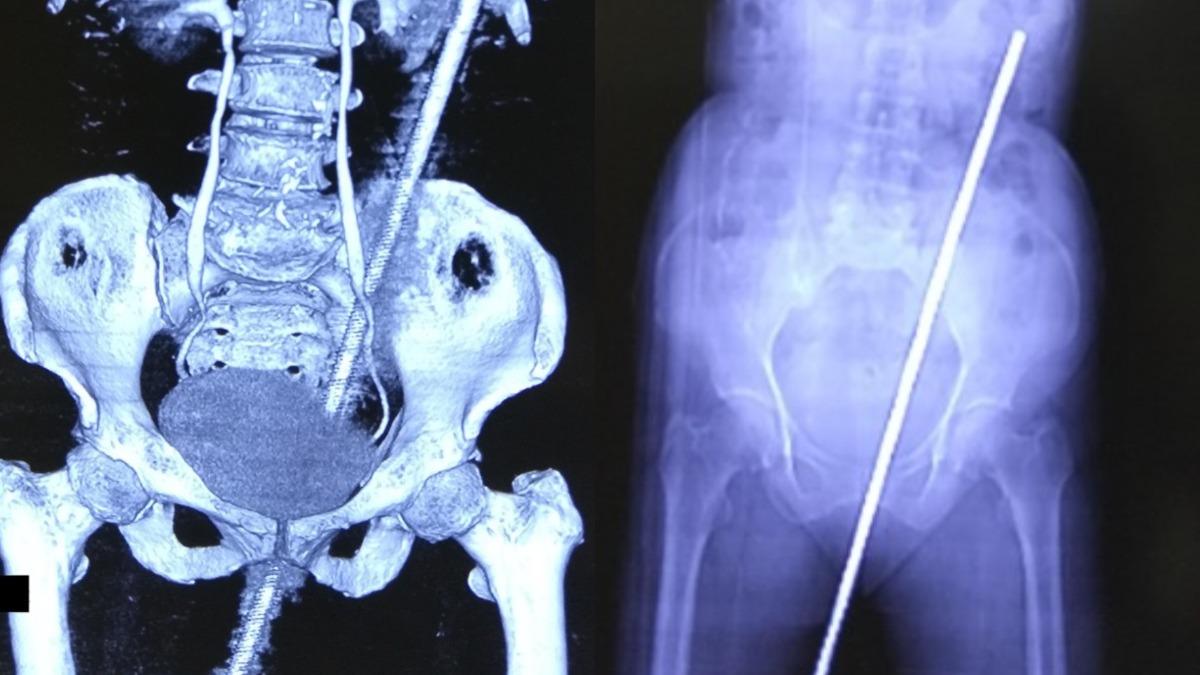

妇女田里突滑倒 遭60公分铁棍贯穿后门

(新德里12日综合电)印度一名妇女在田里行走时不小心跌了一跤,当场跌坐在身边一根沾满牛粪和泥土的生锈铁棍上,直接从臀部贯穿至体内,痛的她狂喊救命。幸好没有伤到重要器官,她在动手术抢救后休养了10天获准出院。

这根约有60公分长的铁棍平常放在田里用来支撑藤蔓,因此早已布满锈斑、泥土、肥料甚至是牛粪,妇女一屁股坐上去时立即被贯穿臀部,紧急送医后发现肛管、直肠已被刺破,幸好输尿管、主动脉以及肾脏等重要部位都没有受伤。

在卡斯图尔巴医学院医疗团队的抢救下,贯穿臀部的铁棍顺利被移除,打了破伤风针及抗生素以避免感染后,妇女在医院内接受观察及休养,10天后获准回家,除了初期的恶心、腹痛、无法行走外,目前她已经逐渐恢复正常。